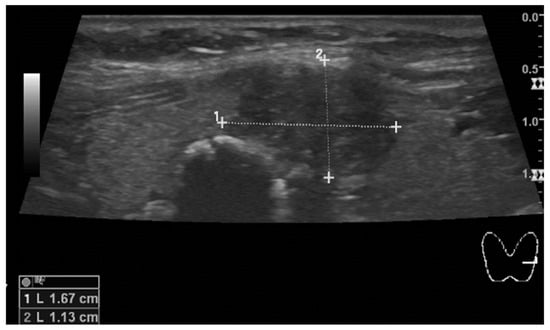

2. Case Presentation